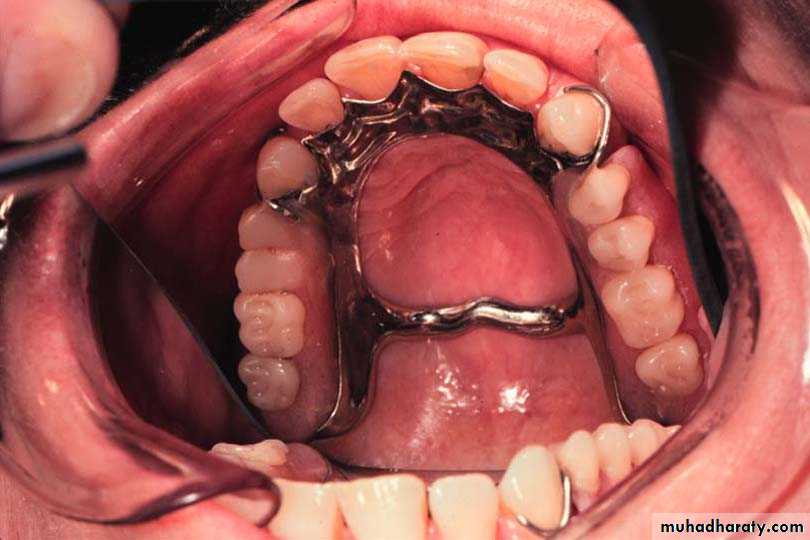

4-Anteroposrerior palatal strap(( closed horseshoe)) (cl I, II, III)

Design

1.The anterior strap should be positioned as back as possible on the rugae area.

2.The posterior strap should be placed as far back as possible on the hard palate.

3.The borders of the connectors should be placed 6 mm away from the gingival margins or should extend above the height of contour of the teeth

4-Relatively broad(8 to 10 mm) anterior and posterior palatal straps

5-Lateral palatal straps (7 to 9 mm) narrow and parallel to curve of arch.

6-Anterior palatal strap follows the valleys of the rugae at right angles to the median palatal suture.